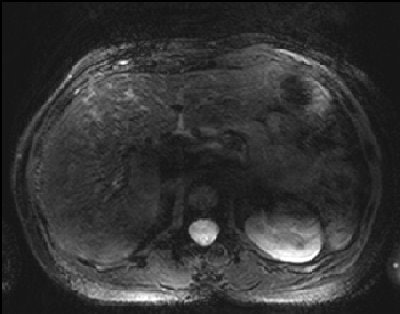

Their analysis found that of the noncontrast-enhanced MR images, 2D FLASH imaging had the highest mean scores for overall image quality (mean score of 4.52), for vessel delineation (mean score of 4.22), and for phase imaging (mean score of 4.40).

Researchers also found that T2-weighted TSE imaging resulted in the greatest image impairment with a mean score of 3.92, "falling short of diagnostic relevance and precluding a clinical application." T2-weighted TSE imaging results were "significantly inferior" to both 2D FLASH and 3D FLASH images.

Dynamic 3D FLASH imaging yielded good contrast enhancement of the liver and improved visualization of the liver's arteries and veins, while the portal veins were well defined in nonenhanced and all phases of dynamic imaging.

"Our qualitative image analysis revealed strong differences between T1-weighted and T2-weighted imaging with regards to image quality, conspicuity of anatomical details, and presence of artifacts," Umutlu and colleagues concluded. "In this study setup, 2D FLASH imaging provided best overall image quality regarding contrast resolution, sharpness, and clarity.'